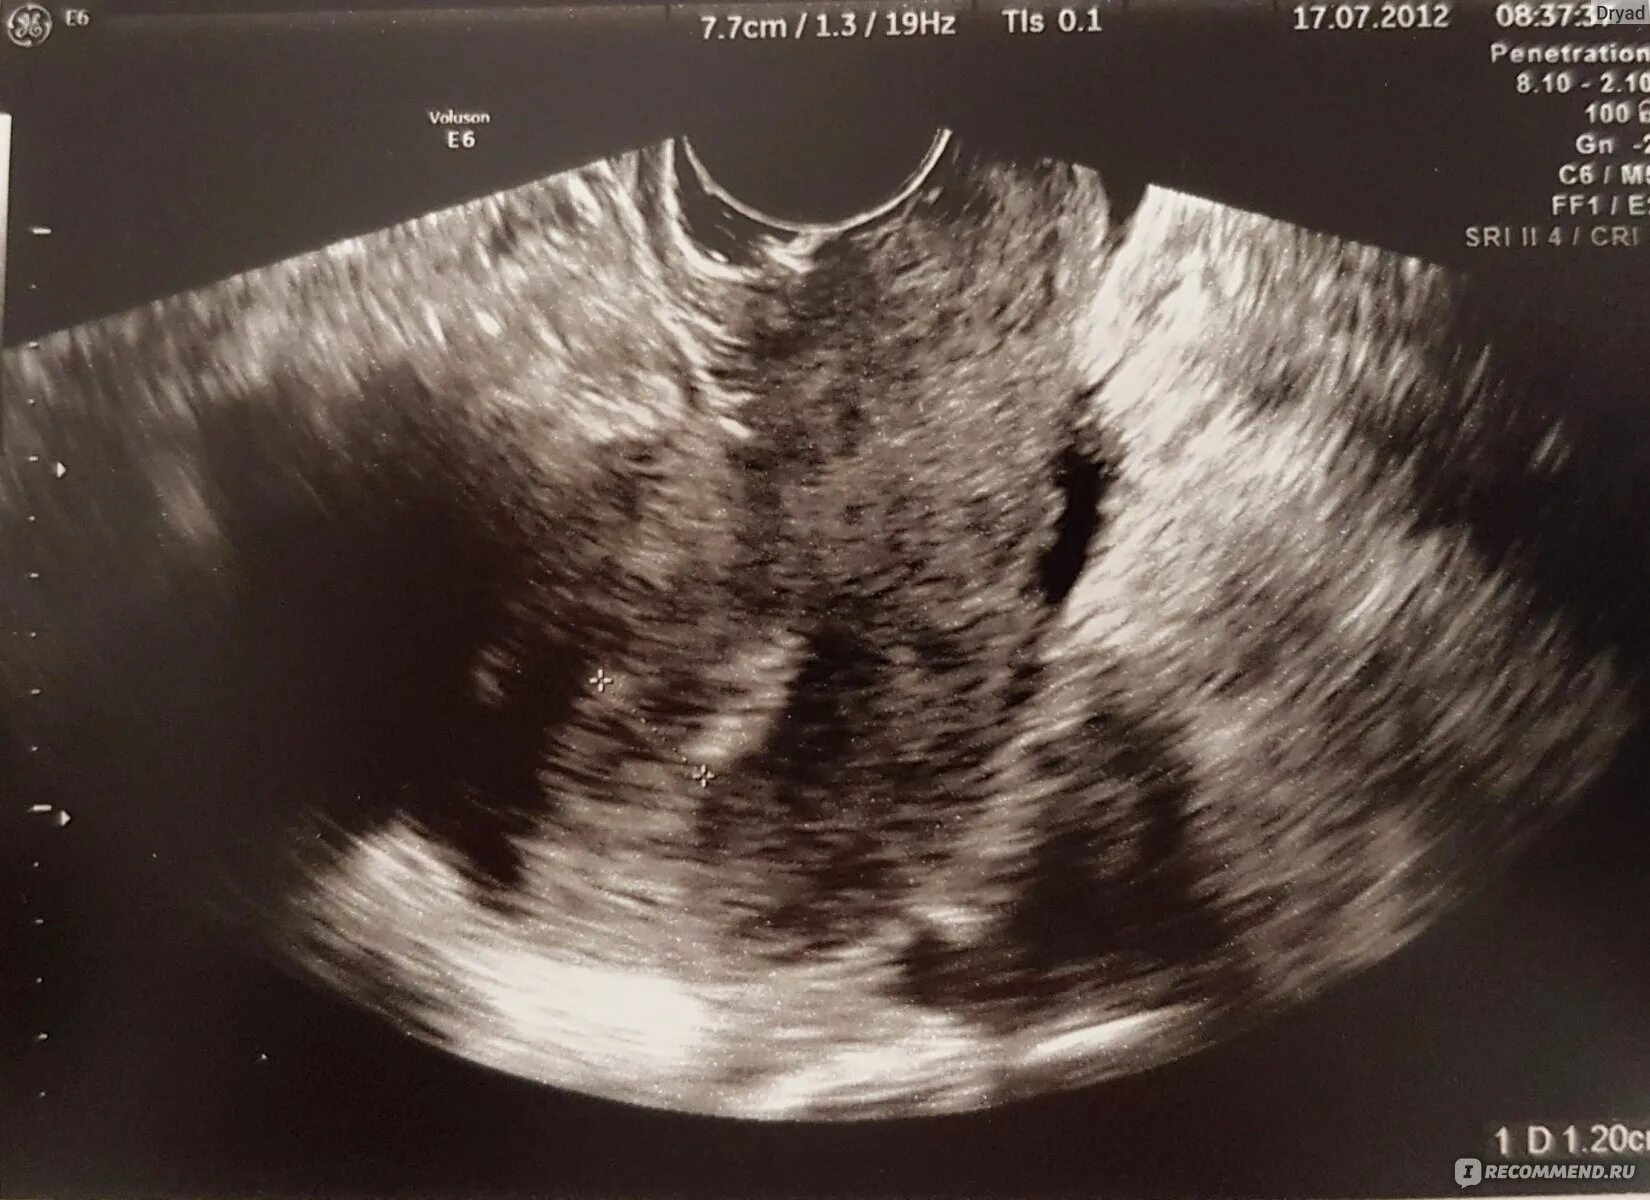

Как убрать полипы в матке без операции